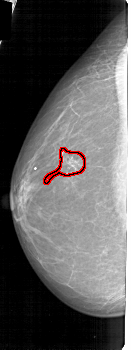

FILE: A_1178_1.LEFT_CC.OVERLAY

TOTAL_ABNORMALITIES 1

ABNORMALITY 1

LESION_TYPE CALCIFICATION TYPE FINE_LINEAR_BRANCHING DISTRIBUTION SEGMENTAL

ASSESSMENT 5

SUBTLETY 5

PATHOLOGY MALIGNANT

TOTAL_OUTLINES 1

BOUNDARY